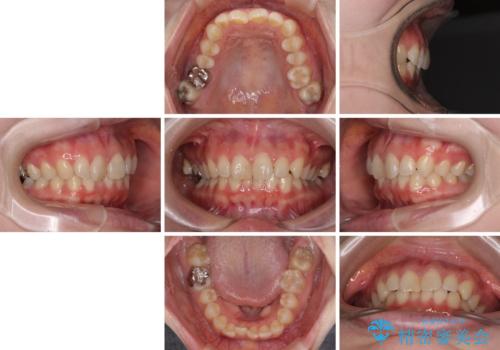

- 近々転勤の予定があるが、早めにインビザラインによる矯正治療を始めたいとのことで来院された患者様です。

上下ともにデコボコの程度は著しいものではなく、インビザラインで十分に対応可能な歯列不正でした。

後戻りによりスペースができてしまうことを避ける目的で、IPR(歯と歯の間を削る)を極力用いない矯正治療を行うこととしました。